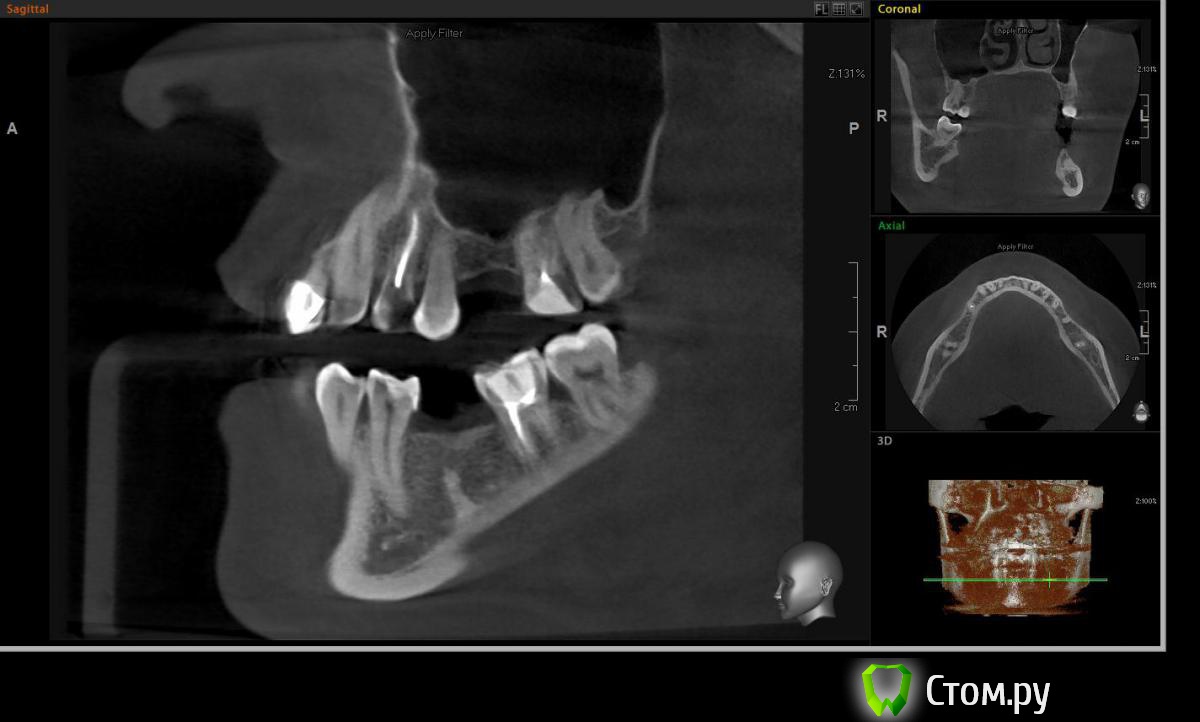

Евгений Ходыкин Опубликовано 19 октября, 2014 Поделиться Опубликовано 19 октября, 2014 Всем привет. Кто сталкивался подскажите плиз что за образование и как отразится на постановке имплантата. Вроде подобное что-то обсуждалось, но перестрахуюсь Ссылка на комментарий

Чертков Александр Опубликовано 20 октября, 2014 Поделиться Опубликовано 20 октября, 2014 Остеома или конденсирующий остит. На имплантацию никак не повлияет. Повлияет вестибулярный дефект гребня 2 Ссылка на комментарий

Михаил Демурчян Опубликовано 24 октября, 2014 Поделиться Опубликовано 24 октября, 2014 (изменено) Похоже на гиперцементоз. Возможно также, имеется осколок корня удаленного 3.6. Изменено 24 октября, 2014 пользователем Михаил Демурчян Ссылка на комментарий